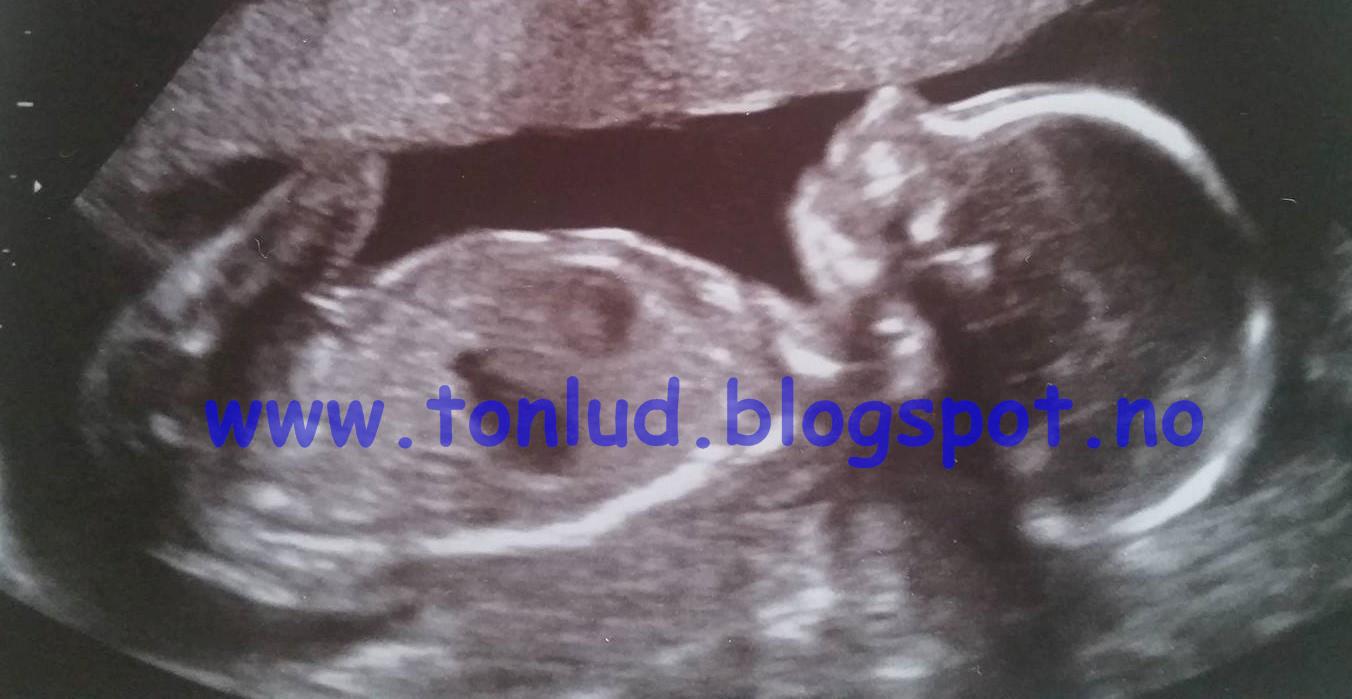

Så her er det stor familieglede i "Det Gule, Kule Huset", og både små og store gleder seg til lillebror som kommer i april. Lille Store Lykke gleder seg veldig til å bli storesøster, og har vært min gode hjelper i hele høst. Smører brødskiver til meg, kommer med drikke til meg, passer på at jeg ikke stresser meg opp, synger for magen og er veldig fornøyd med at hun endelig skal få en lillebror.

Da er det på tide å røpe hemmeligheten her på bloggen også. Det var ikke bare noen hvilken som helst sykdom som satte en stopper for min "Hell Week" ala Bertrand Larssen, men et lite bøllefrø som skapte kvalme og dårlig form i mors mage. Han har egentlig fortsatt å bølle med meg hele høsten, selv om kvalmen heldigvis har gitt seg. Derfor har det heller ikke blitt noen ny helvetesuke denne høsten, men jeg kommer sterkere tilbake når alt ligger mer til rette for det.